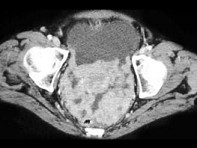

55岁,女性,结合图像,最可能的诊断是()

• A.卵巢癌扩散

• B.结核性腹膜炎

• C.胃癌

• D.腹膜炎

• E.以上都不是